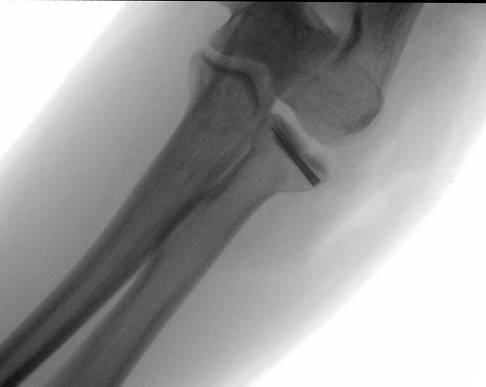

Apparative bildgebende Diagnostik: Röntgen

Die Standarduntersuchung ist die Röntgenaufnahme des Ellenbogens in zwei Ebenen. Dabei wird eine a.-p. Aufnahme angefertigt (anterior-posterior, d. h. der Strahlengang verläuft von von vorne nach hinten durch das Ellenbogengelenk). Zudem erfolgt eine seitliche Aufnahme des Ellenbogengelenks. Einfache Frakturen (Fraktur-Typ 1 und 2 nach Mason) können mit der Röntgenaufnahme sicher diagnostiziert werden.

Ist der Bruch nicht sicher im Röntgenbild zu beurteilen oder liegt ein komplizierter Bruch oder gar eine Zertrümmerung des Radiusköpfchens vor, erfolgt zusätzlich eine Computertomografie (CT)/digitale Volumentomografie (DVT).